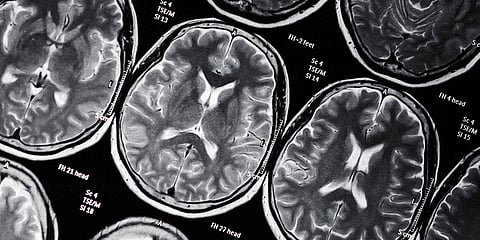

Radiologists create a segmentation mask to diagnose and treat brain tumors. These masks are essentially an image that is used to mark the exact location of cancerous growths. It also helps in creating a treatment plan.

Making the use of deep learning models, Peltarion is assisting radiologists to create these masks quickly and accurately. The technology used can help with the segmentation process. It will also enable doctors to work more efficiently when it comes to radiotherapy treatment.

According to Brinne, "In simple terms, you train a deep learning model with data—in this area, you train the models with a lot of images which are well labeled with data on the brain tumor, its characteristics and where it is displayed."

These models are quick to run and are basically free from errors. For a new case, the deep learning model forecasts the appropriate segmentation mask and suggest where the tumor is present and how treatment can be applied to it.